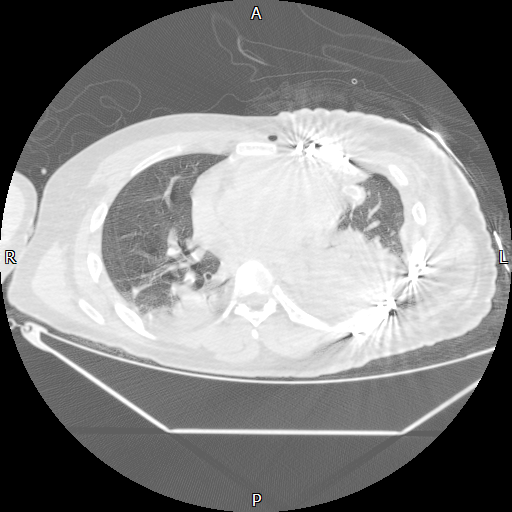

在重症监护室观察30多小时后,小刘转回普通病房。尽管性命得保,但术后第二关——“肺部感染”接踵而至。CT显示,历经创伤与手术,他的左肺萎缩成一团,胸腔充满渗出液。若不及时进行呼吸康复,积液极易演变为脓胸,导致严重感染。

术后第2天胸部CT提示左侧胸腔积液、肺不张

术后第10天胸部CT提示左侧胸腔微量积液,肺基本张开